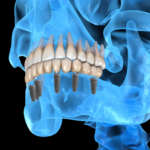

I vantaggi della chirurgia guidata in implantologia

L’apprendimento della chirurgia guidata e dei nuovi protocolli digitali è molto meno complesso di quanto si possa immaginare....